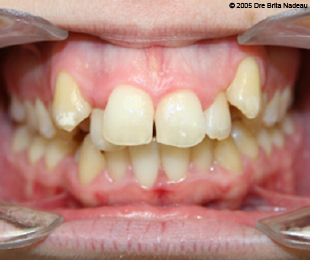

Marie-Hélène Cyr - Central intraoral view - Before orthodontic treatments and orthognathic surgeries (November 24, 2005)

November 24, 2005 - My teeth during my consultation appointment with my orthodontist.